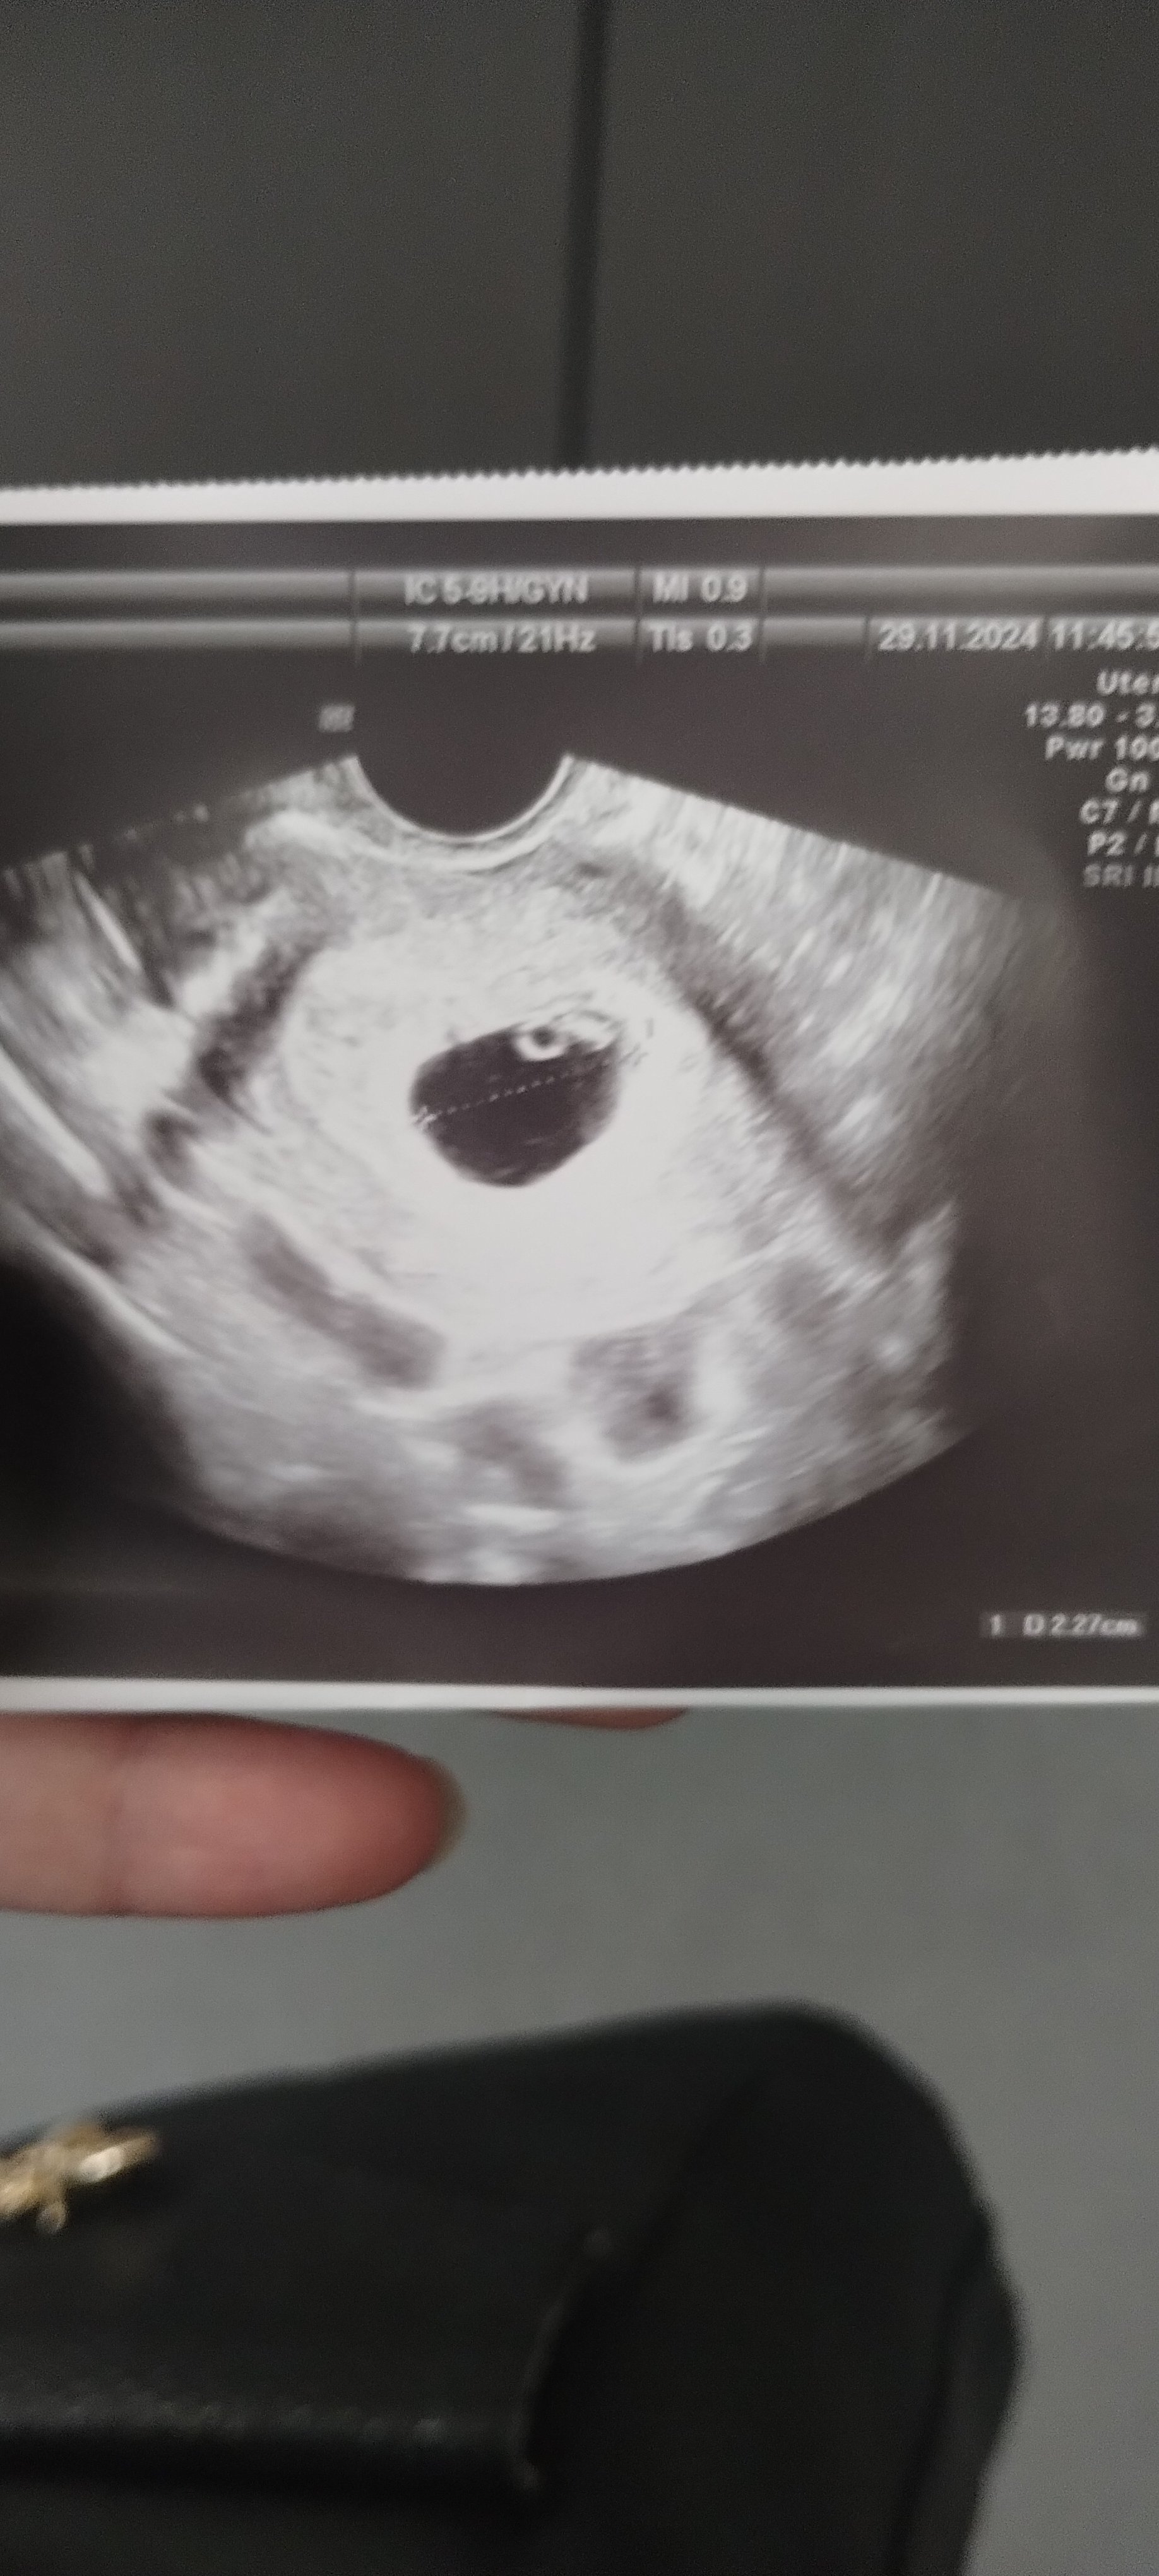

P.s nie wiem czy dobrze zdjęcie dodałamJa już po, lekarz powiedział, że nie ma jeszcze zarodka i mam wrócić we wtorek, wtedy już będzie z akcją serca... Ale ogólnie wygląda, że wszystko w porządku ... Myślałam, że ta "plama" obok kółeczka to zarodekno nic, czekam do wtorku

Według om 6+4, jeśli liczyć od owulacji to 6+2A który to tydzień? Ja na początku poszłam w 5+5 (tak wskazywała aplikacja) też nie miałam jeszcze zarodka. Tylko pęcherzyk żółtkowy. Byłam zestresowana i oczywiście zaczęłam panikować. Poszłam tydzień później i okazało się na USG, że jest dopiero 6+1 i miałam już zarodek z serduszkiem

No to pewnie będzie już lada moment a do wtorku szybko zleciWedług om 6+4, jeśli liczyć od owulacji to 6+2